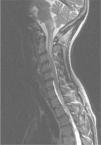

Focalidad neurológica en una paciente con lupus eritematoso sistémico

E. García Melchor, B. Mora Peris, G. Espinosa Garriga

Servicio de Enfermedades Autoinmunes. Hospital Clinic. Barcelona. España